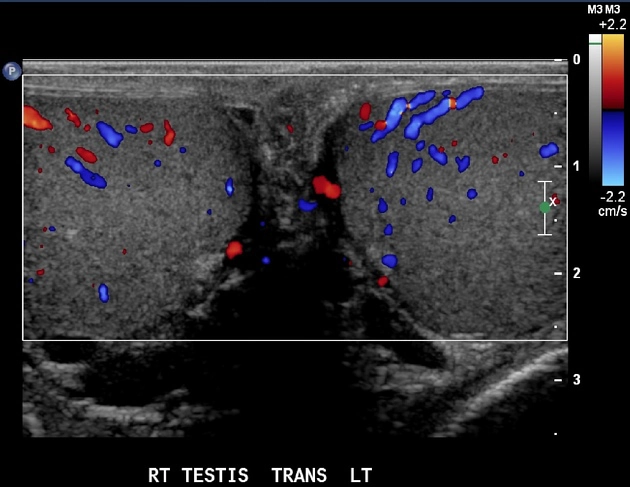

• Khối u tinh hoàn

Ung thư tinh hoàn (Testicular cancer)

Lymphoma tinh hoàn (Testicular lymphoma)